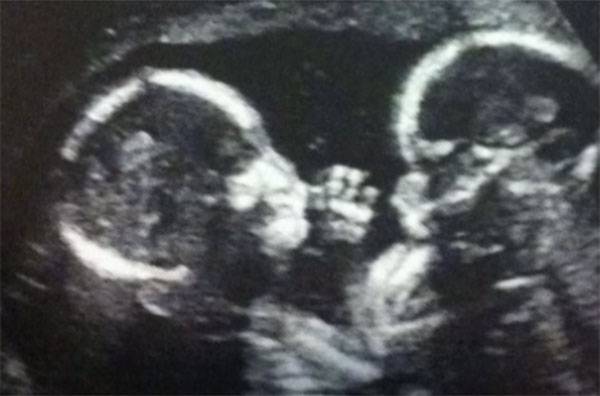

Durante un’ecografia a ultrasuoni le bambine, chiamate dai genitori River e Piper, sono risultate essere gemelle monoamniotiche. Questo vuol dire che, oltre ad essere gemelle, condividevano anche placenta e sacco amniotico. Si tratta di una condizione molto rara e pericolosa.

Le gemelle non avevano una membrana divisoria, il che voleva dire che il loro cordone ombelicale non poteva essere separato e mentre gli embrioni si sviluppavano i loro cordoni venivano girati e arrotolati intorno a ciascuna delle due finendo col formare una treccia che era estremamente pericolosa, dal momento che un cordone poteva comprimerne un altro causando la morte”.

Ecco le due piccine: